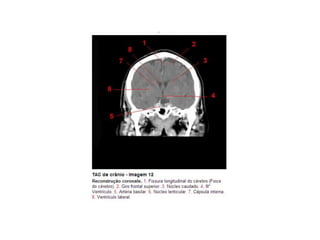

Anatomia E Protocolo Tomografia Computadorizada de Crânio PPT

Anatomia Seccional do Crâneo em Tomografia Computadorizada PPT